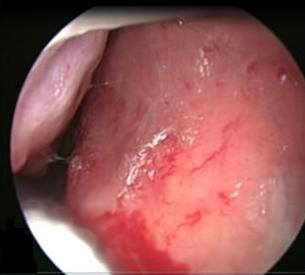

It is an autosomal dominant vascular disorder, which has a variety of clinical manifestations, with epistaxis being one of the most common. Many treatment options exist for epistaxis, but with no consensus on which is the method of choice. We describe the case of a patient with hereditary hemorrhagic telangiectasia (HHT) secondary epistaxis with septoplasty managed with synthetic hard graft, which improved intensity and frequency of bleeding episodes. This technique is a variant of the septodermoplasty described by several authors, but the use of synthetic dura can help in obtaining better results and avoid taking skin grafts from other sites different from the surgical site.